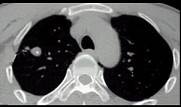

- 单项选择题男性,25岁, 低热、咳嗽2个月。胸部CT见图,最可能的诊断是 ( )

A、急性血行播散型肺结核

B、肺结核球

C、肺癌

D、肺脓肿

E、支气管扩张